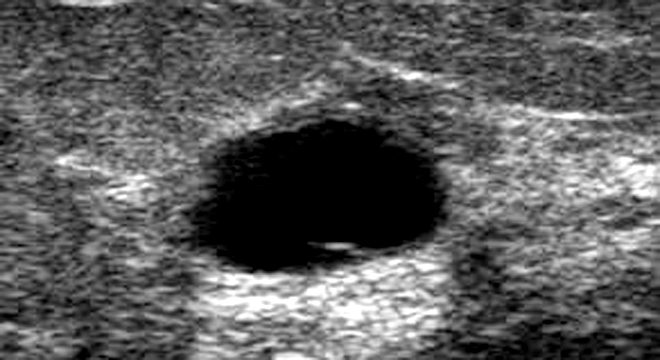

- Ekografia

Gjiri është i përbërë nga indi lidhor dhe gjendrat. Kur shfaqet mastopatia, kjo përbërje ndryshon. Shtimi i indit lidhor çon në formimin e kokrrave, ndërkohë që ndryshimet në nivelin e gjendrave shkaktojnë formimin e kisteve. Shpesh, bëhet fjalë për një kombinim të kokrrave dhe kisteve.

- Rrjedhja e lëngut pas shtypjes së thithit të gjirit, që tregon për praninë e kisteve në brendësi të tij.